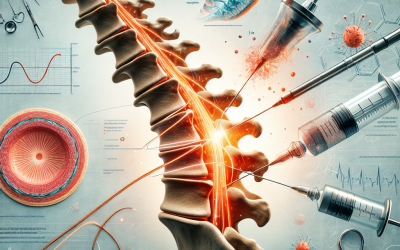

Evaluación de resultados prospectivos en el mundo real en pacientes tratados con ablación de radiofrecuencia lumbar por dolor crónico (rápido)

Resumen Antecedentes: El síndrome de la articulación de la faceta lumbar (LFJ) es una de las formas más comunes de dolor lumbar crónico. A pesar de varias décadas de uso del mundo real y una gran cantidad de estudios publicados, todavía existe un debate sobre la...